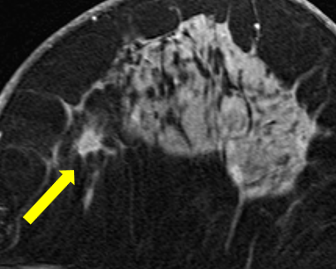

そこで私たちは、そのことを患者さんにしっかり説明し、苦痛をできるだけ少なくするために鎮静剤を使いながら、大腸カメラを定期的に受けていただくことにしました。すると、なんと!とても早い段階(ステージ0)の大腸がんを見つけることができ、無事に早期治療まで進めることができました。

実は、私が大学院生のころに発表した研究(Harada Akira, et al. J Gastroenterol Hepatol. 2018)でも、食道に同じような変化があった方に乳がんのリスクを丁寧に説明し、検査を続けていただいたことで、初期の乳がん(ステージ1)を早期に発見して、完治したというケースもあります。